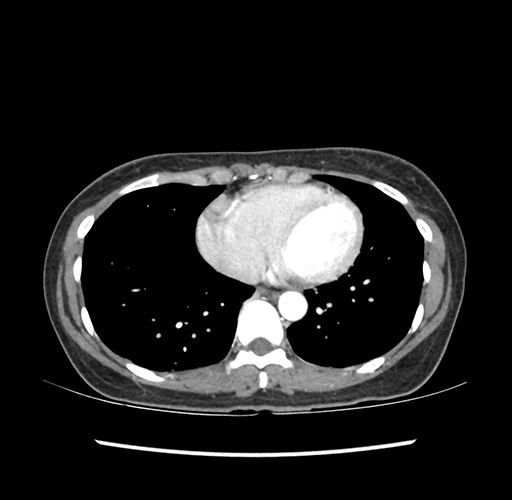

Imaging Analysis

Look through the patient's CT scan to identify any areas of concern for the necessary procedure.

Based on your CT findings, which issue(s) would give reason for "planned slowing down moment(s)" in this case?

Considering a standard left lateral sectionectomy procedure, what step(s) of the operation would you do differently in this case ?